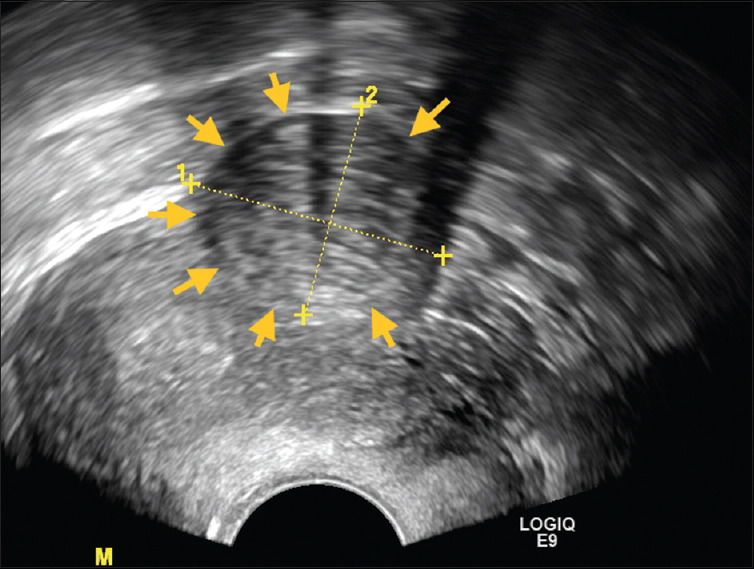

Uterine Adenomatoid Tumor: A Great Imitator of Leiomyoma under Laparoscopy.

子宫腺瘤样肿瘤:腹腔镜下平滑肌瘤的巨大模仿者